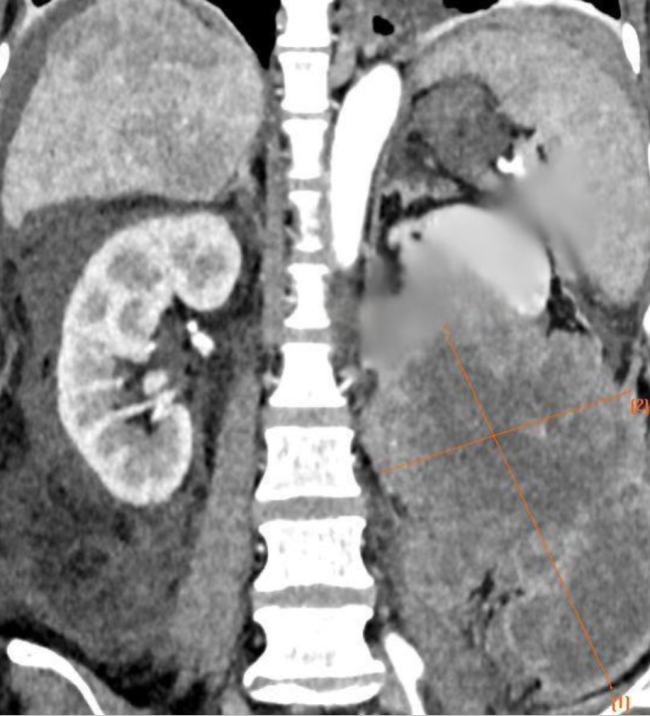

CT结果让人震惊:她的左肾里,长着一个18cm的巨大肿瘤,比约9cm的正常肾脏整整大了2倍,腹腔、盆腔满是积液,结肠被挤压变形——她虚弱到无法行走,吃不下一口饭,人消瘦至40公斤。

第三,患者处于严重的恶液质状态,并伴有感染。加之手术创面极其巨大——从脾脏下缘一直延伸到盆腔,整个左侧腹腔都是手术区域。无论是肿瘤侵犯的区域,还是因炎症形成的脓腔,都是手术无法回避的挑战。